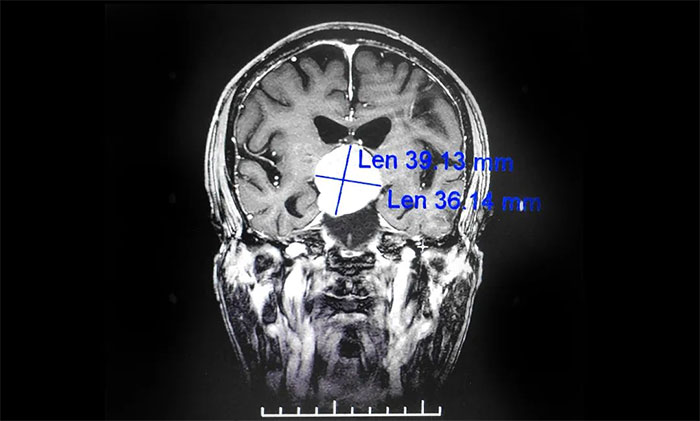

▲ 鞍區(qū)囊性占位病變

通過進(jìn)一步完善頭顱磁共振檢查,提示患者鞍區(qū)囊性占位病變,考慮為顱咽管瘤,瘤體最大直徑超過4cm。